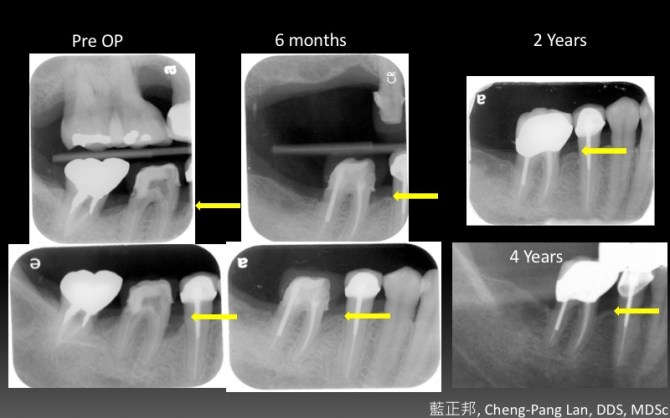

●第八章就是Buser最著名的Early implant placement in the esthetic zone,完整分類風險等級、挑選案例、單顆植體、多顆植體的前牙手術考量。更加入了超過十年的術後追蹤。我認爲Buser在這塊領域的貢獻非凡,是整本書的精華所在。